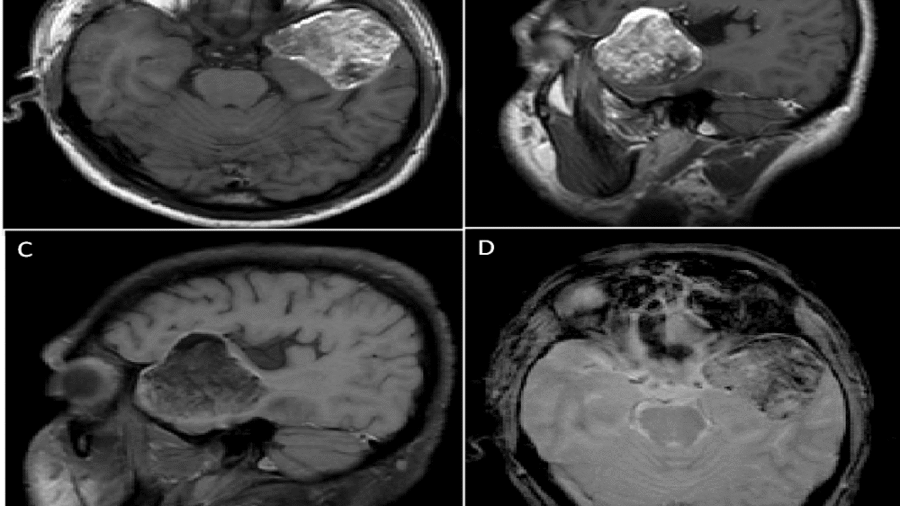

39 years , male, presented with progressive gait disturbance and speech difficulty since 11 months. Associated with headache, giddiness and vomiting since 3-4 months.